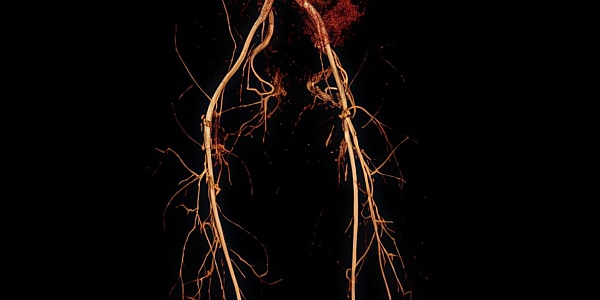

Сосуды нижних конечностей